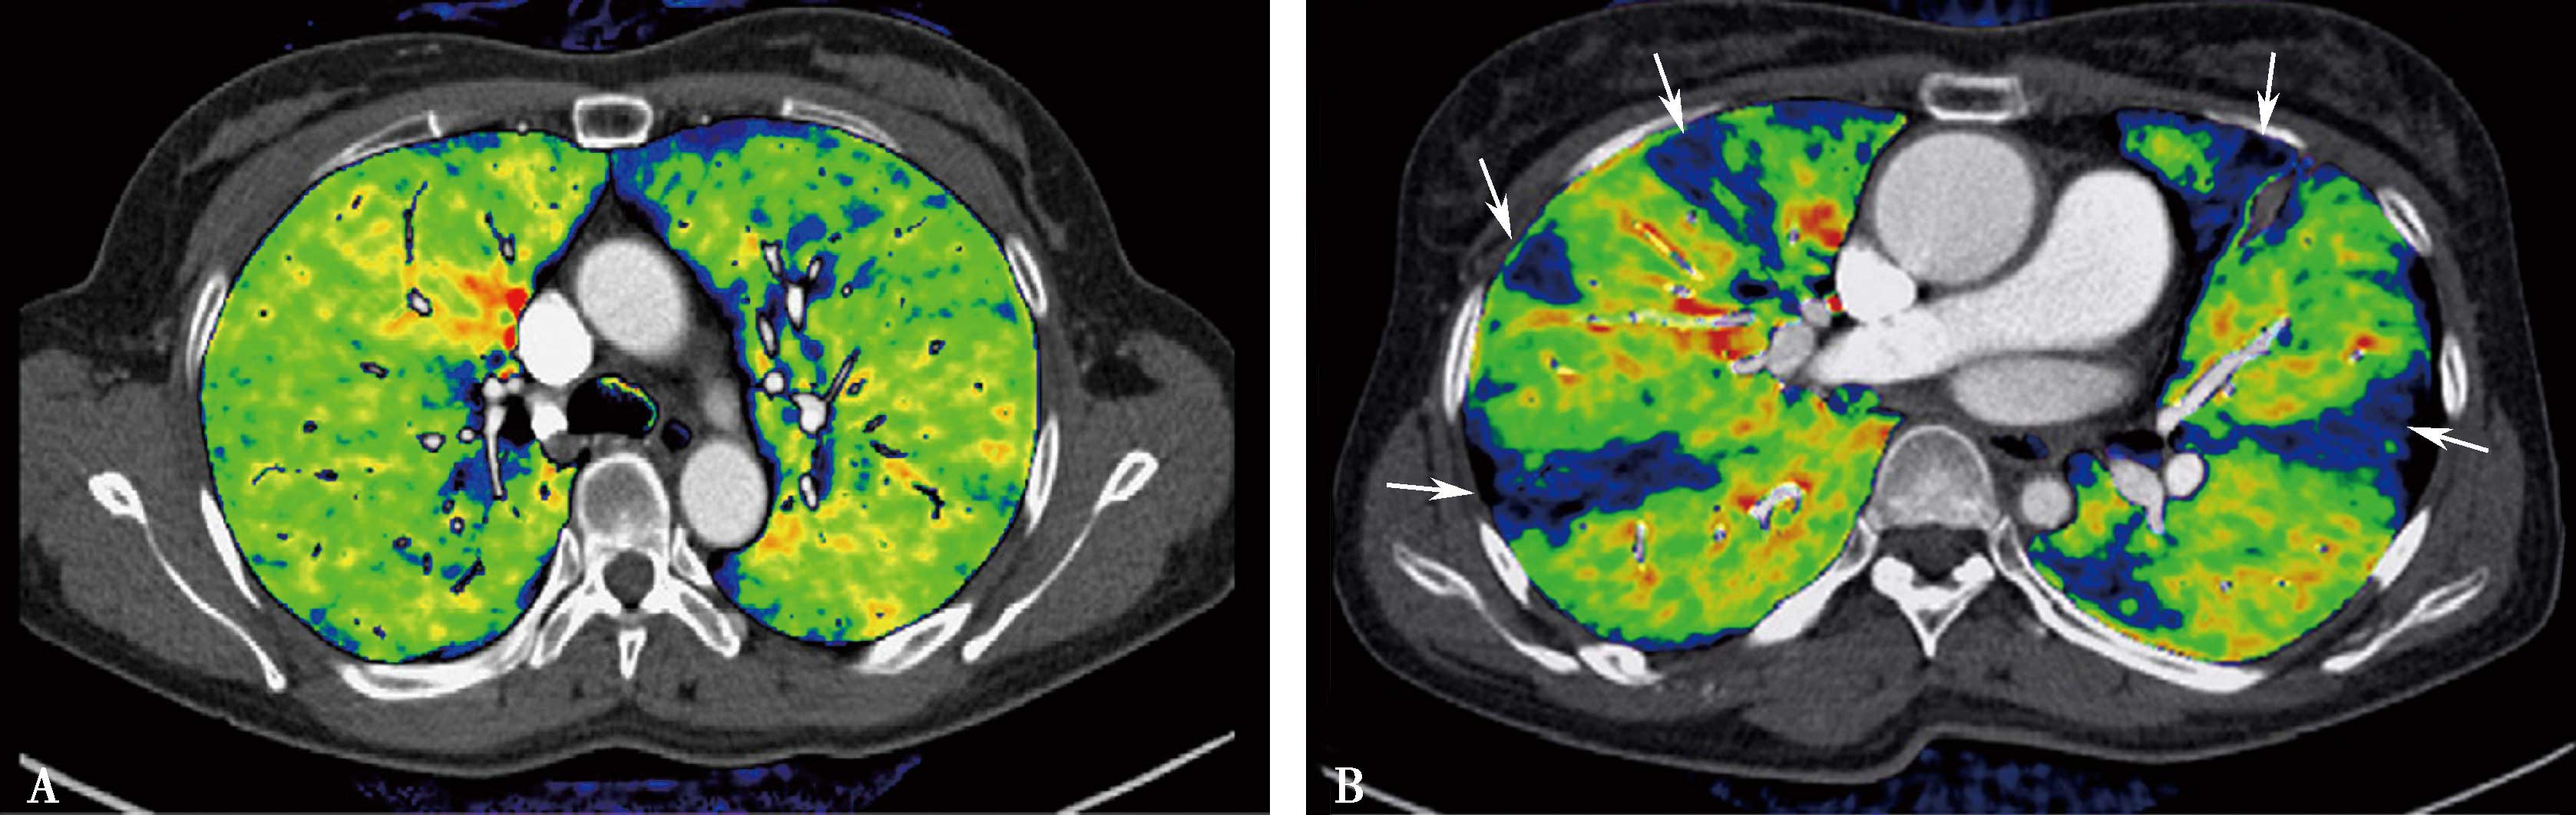

2.CT肺灌注成像肺栓塞的诊断应用 CTPA及肺部灌注成像可以显示肺动脉管腔形态,可以显示肺栓塞所引起的肺动脉形态学变化,同时提供栓塞后肺组织微循环改变,并以灌注伪彩图的形式直观地显示栓塞引起的灌注缺损区,为诊断及治疗提供更多信息,指导治疗,评价治疗效果。但CT肺灌注成像不能直接显示栓子的部位和大小,诊断应该结合CTPA所显示的肺动脉狭窄及梗阻,做出诊断。但是,研究表明灌注扫描对检出亚分段的栓塞,可以提高CTPA诊断敏感性(20%),有重要价值。与核素对照研究,高度相关( r =0.884)(图8-3-2~图8-3-6)。

图8-3-5 肺栓塞双能CT肺灌注成像(DELPI)

CTPA显示左肺舌叶段-亚分段、下叶内前基底段-亚分段未显影(A↑),灌注扫描示相应肺段灌注缺损(B↑),明确左肺舌叶段-亚分段、下叶内前基底段-亚分段肺栓塞诊断

图8-3-6 肺栓塞双能量CT能谱成像

A.右肺下叶外基底段栓塞(↑);B.能谱成像得到肺碘基物质图,梗阻肺段呈低灌注,清楚反映栓塞分布、程度(↑)